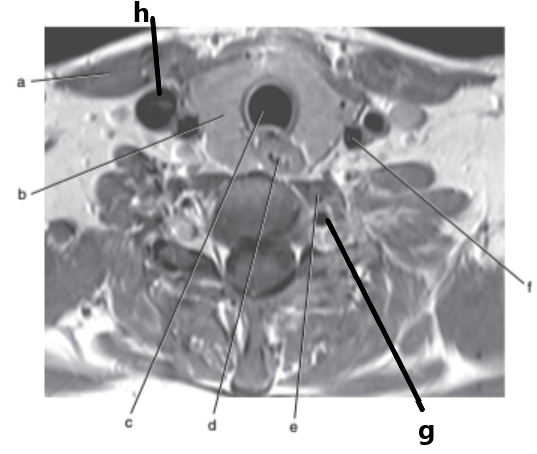

What imaging plane is this ?

transverse

What is letter a ?

Internal jugular vein

What is letter h ?

What is letter f ?

Spinal cord

What is letter g ?

Thyroid gland

Vocal cords